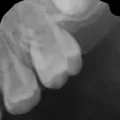

Кариес имеет свойство развиваться, что будет через 6-12 месяцев никто не знает, думаю, ничего хорошего. Фторирование не имеет смысла при уже существующем кариесе. Наркоз при лечении зубов у детей довольно распространенная процедура, не стоит бояться, а наоборот необходимо принять все возможные варианты для избавления от кариеса.